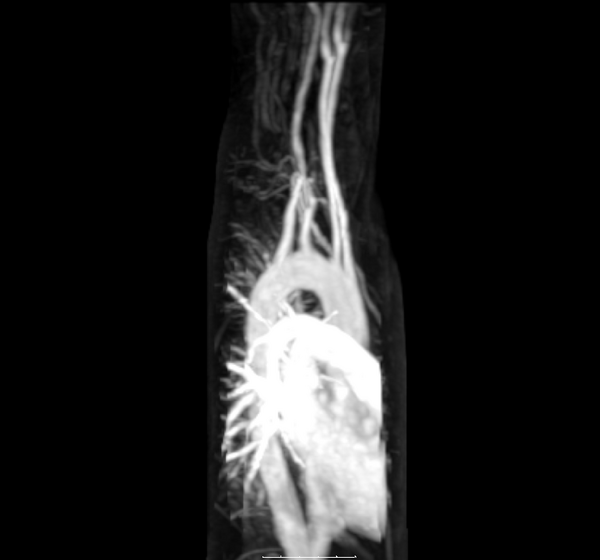

Большой круг кровообращения — это часть сердечно-сосудистой системы, которая переносит насыщенную кислородом кровь от сердца через аорту из левого желудочка, где кровь ранее депонировалась из малого круга кровообращения, в остальную часть тела и возвращает обедненную кислородом кровь обратно в сердце[10].

Насыщенная кислородом кровь поступает в большой круг кровообращения при выходе из левого желудочка через аортальный клапан[15]. Первой частью большого круга кровообращения является аорта, массивная и толстостенная артерия. Аорта изгибается и разветвляется, снабжая кровью верхнюю часть тела, пройдя через аортальное отверстие диафрагмы на уровне десятого грудного позвонка, входит в брюшную полость[16]. Затем ветви аорты спускаются в живот, таз, промежность и нижние конечности[17] .

Стенки аорты эластичны. Эта эластичность помогает поддерживать кровяное давление[18]. По мере того как аорта разветвляется на более мелкие артерии, их эластичность продолжает снижаться, а растяжимость увеличивается[18].